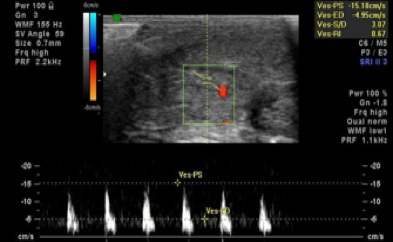

Tendo em consideração que os órgãos sexuais são unidades funcionais dinâmicas cujo funcionamento salutar depende muito da qualidade do aporte sanguíneo que recebem e das gestão fisiológica do citado fluxo, é fundamental, antes de se decidir pela via de intervenção mais adequada ao problema sexual apresentado, realizar uma avaliação, direta (Tac, RMC, Ecografia, Ecodoppler, angiografia...) ou indireta (avaliação de sinais e sintomas) de todas as estruturas vasculares envolvidas no ciclo de resposta sexual.

Todas as situações que envolvam o diagnóstico de um problema vascular que condicione determinantemente o bom funcionamento genital/sexual, o paciente é prontamente encaminhado para uma Consulta de Urologia e/ou em casos mais específicos para um especialista em Cirurgia Vascular.

Nota – O surgimento de problemas vasculares que afetam o bom funcionamento sexual é muito mais comum nos indivíduos do sexo masculino (porque o pénis é um órgão que depende funcionalmente da existência de um bom fluxo sanguíneo e da ausência de refluxos acentuados), em doentes crónicos (Diabéticos, Hipertensos, Arterioscleróticos...) e em pacientes idosos (pelo facto de terem tendência para desenvolver uma ou mais do que uma das patologias crónicas anteriormente citadas).